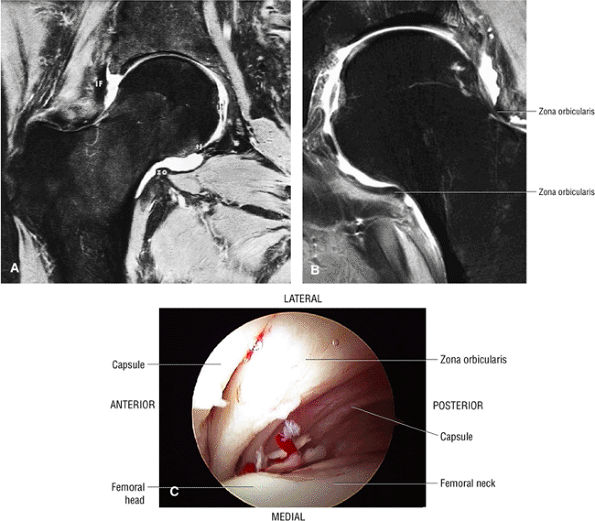

FIGURE 3.57 ● (A) Coronal MR arthrogram displaying hip joint and capsular anatomy. The distal insertion of the capsule is at the base of the femoral neck. The zona orbicularis (zo) is seen as an area of capsular thickening and tightening over the middle of the femoral neck. The transverse ligament (tl), iliofemoral ligament (IF), and ligamentum teres (lt) are identified. The acetabular labrum is absent. This coronal MR section cuts through the supra-articular recess, the intra-articular recess, and the recess colli (the recess at the base of the femoral neck). Fat-suppressed T2-weighted fast spin-echo image. (B) Coronal FS PD FSE image showing the zona orbicularis fibers at the base of the femoral neck circumferentially surrounding the posterior capsule. The zona orbicularis represents a deep layer of circularly oriented fibers that do not directly attach to the femur. (C) Arthroscopic view of the zona orbicularis.